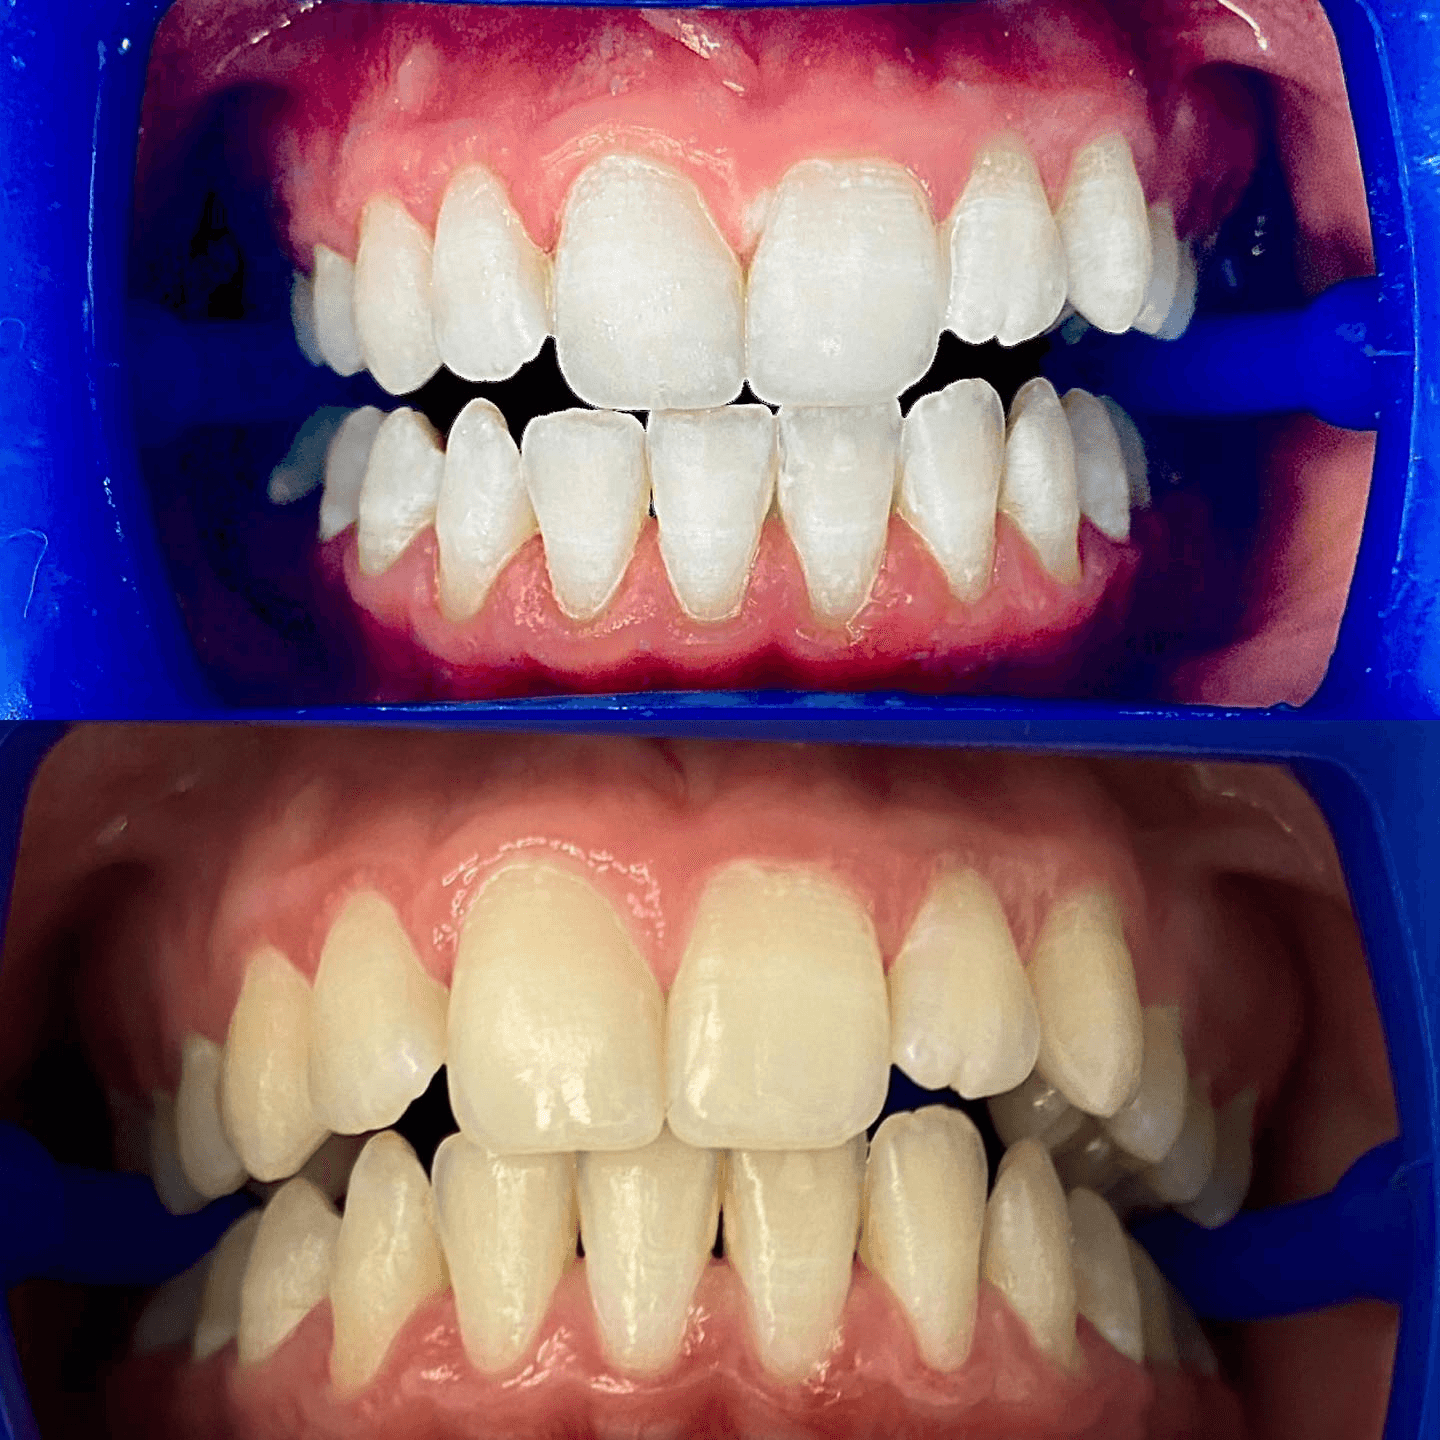

תוצאות - בהסכמה ובטעם טוב

צילומים מהמרפאה - מוצגים בהתאם להסכמות מטופלים ולכללי הפרסום.

חשוב: יש להציג תמונות לפני/אחרי רק בהסכמת מטופלים ובהתאם לכללי הפרסום הרפואי.